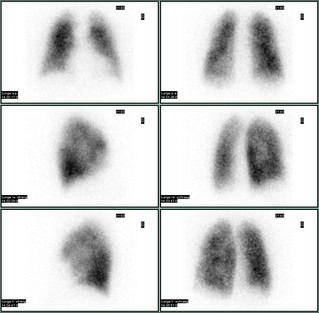

Die Lungenperfusionsszintigraphie dient dem Nachweis evtl. Durchblutungsausfälle beispielsweise bei Lungenembolien und zur Bestimmung der anteiligen regionalen Lungendurchblutung vor geplanten Lungenoperationen.

Die Lungenventilationsszintigraphie stellt die belüfteten Lungenabschnitte dar. Gerade zum Nachweis von Lungenembolien kann es sinnvoll sein, die Lungenperfusions und -ventilation gemeinsam zu untersuchen.